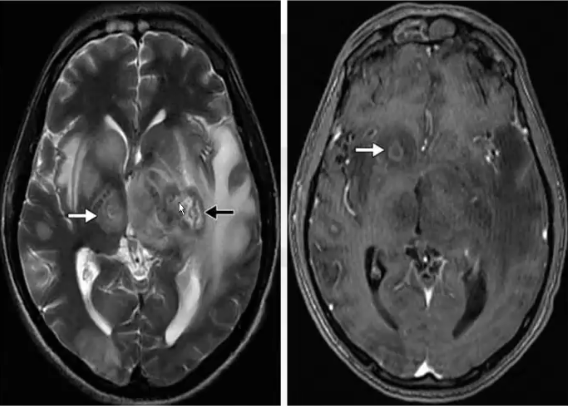

❖ MRI在检测新老病灶方面均比CT更加敏感。在T2上活动性病灶的信号强度各不相同,可呈高信号,与周围水肿难以区分,也可呈等信号或低信号,可见同心圆靶征。T1上呈等信号或低信号。增强后呈环形或结节状强化,偏心性靶征,出血较为少见。